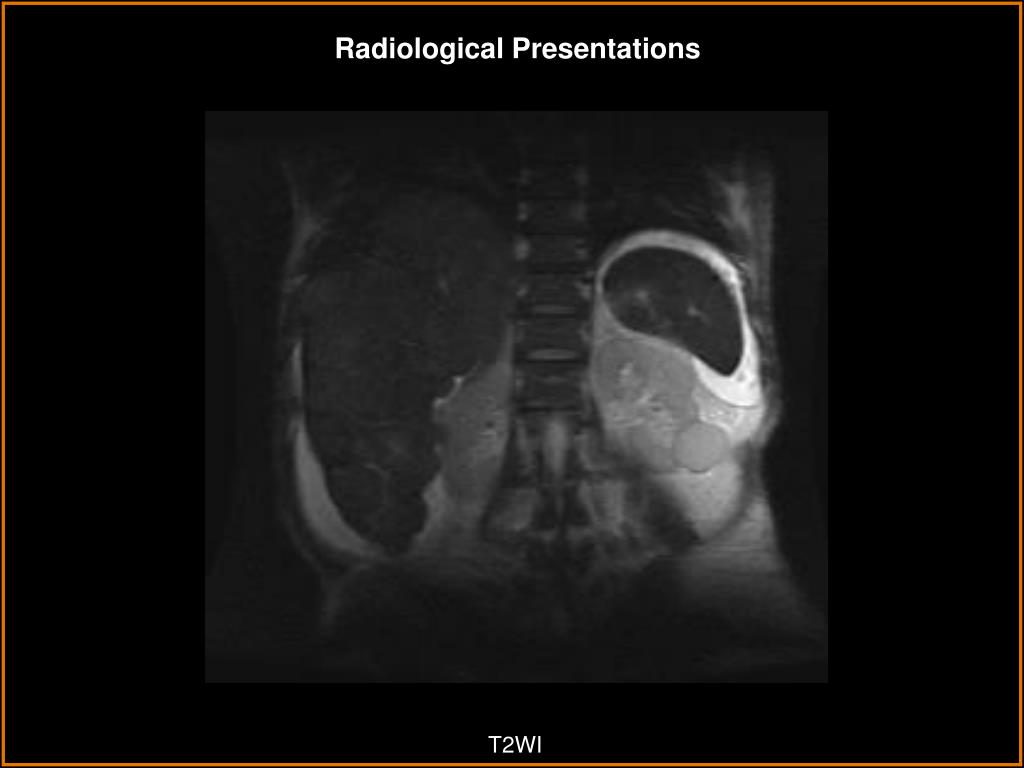

8. Radiological Presentations T2WI

9. Radiological Presentations T2WI

10. Radiological Presentations T2WI

13. Almost the entire liver is replaced by numerous nodules of varying sizes involving all segments of both lobes. The liver is enlarged and macronodular. Some nodules show signal drop-out on the out-of-phase images. Several nodules are hyperintense on both in and out-of-phase, suggestive of hemorrhage within the nodule. There is arterial phase postcontrast enhancement and washing out on the delayed images. Moderate bile duct dilation due to large central masses. Findings and Differentials Findings: Differentials: • Multifocal Hepatocellular Carcinoma • Hepatic Adenomatosis • Cholangiocarcinoma • Nodular Regenerative Hyperplasia • Multiple Hemangiomas • Focal Nodular Hyperplasia • Fibrolamellar Carcinoma • Multiple Metastases

16. MRI Imaging of Adenomas: T1WI: The signal intensity varies form hypo to hyperintense. This is due to the variable fat content of adenomas. T2WI: They are most often hyperintense. This finding is not specific to adenomas. On both modalities, they may also have a heterogeneous appearance due to areas of hemorrhage, necrosis or calcification. Dynamic gadolinum enhanced imaging demonstrates that most adenomas are intensely enhancing during the early arterial phase and are isointense to liver parenchyma on portal venous phase and hypointense on delayed imaging. Signal drop out on out-of-phase or fat suppressed images is a common finding. “Nodule in nodule” appearance. Discussion